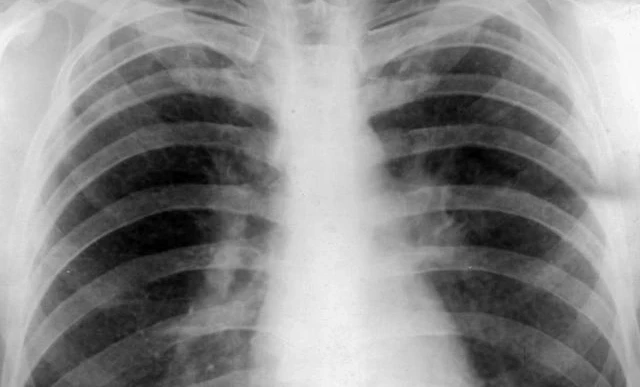

Seluruh anggota keluarga penderita TBC akan disaring, tidak hanya untuk TBC, tetapi juga untuk penyakit penyerta seperti diabetes dan hipertensi melalui pemeriksaan gula darah, tekanan darah, hingga rontgen.

Untuk mendukung upaya tersebut, Kementerian Kesehatan menyiapkan rontgen portabel di wilayah prioritas, termasuk Kota Makassar.